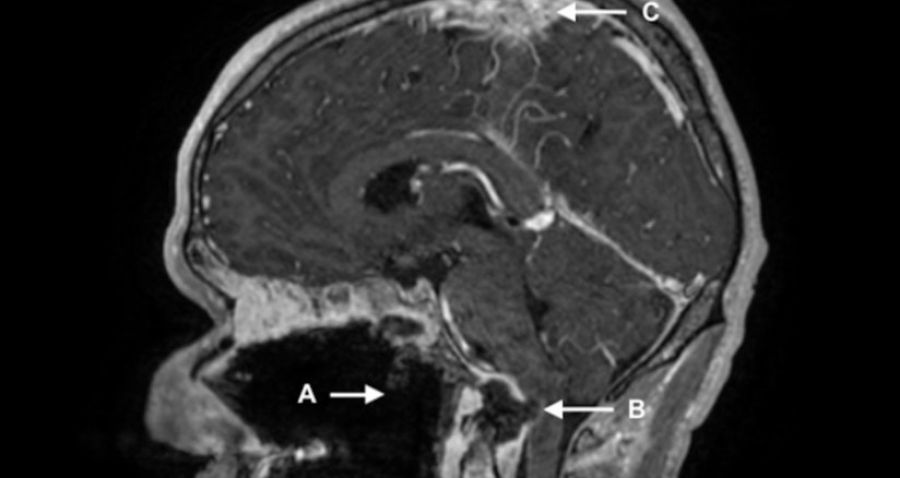

Luego, una tomografía computarizada reveló que el uso frecuente de drogas había destruido por completo su paladar y presentaba una infección bacteriana en los ojos. Luego de siete días de medicación y tratamientos con dos diferentes antibióticos el hombre, cuya identidad no ha sido revelada, fue dado de alta y puesto en contacto con grupos de apoyo para consumidores de drogas.

A pesar de esto, el hombre volvió a emergencias cuatro meses más tarde con una sospecha de sobredosis de estupefacientes. Presentaba una condición potencialmente mortal dado que padecía una lesión cerebral y severos daños en la médula espinal. Exámenes médicos revelaron además presencia de líquido e hinchazón de tejidos blandos en el área donde se conectan el cráneo y la columna. El paciente fue tratado nuevamente con antibióticos; sin embargo, falleció poco después.